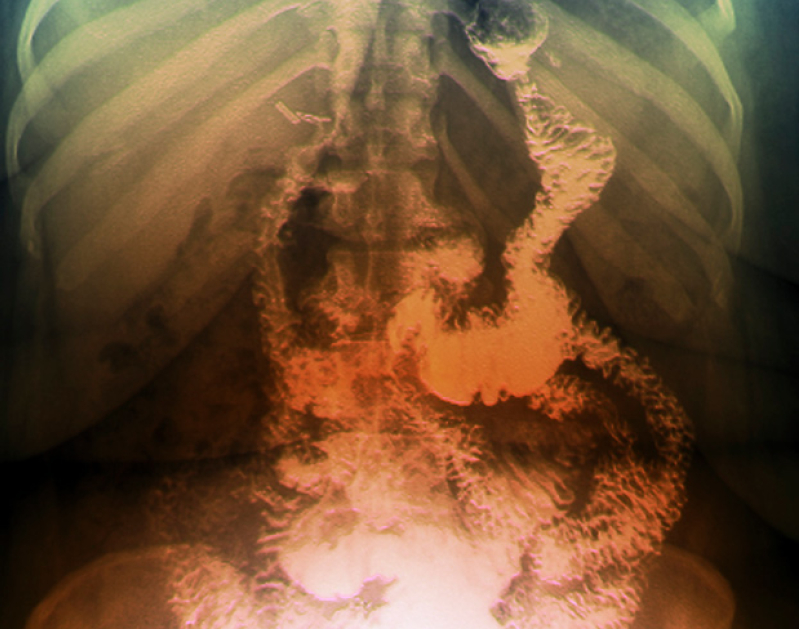

At five U.S. centers, 242 adolescents ages 13 to 19 were enrolled. Most were white females. They had an average body-mass index (BMI) of 53, which would, for example, be a 5'3" teenager who tips the scale at 300 pounds.

All were treated with one of two bypass procedures. There was no control group.

After three years, their average weight had gone from 325 pounds before surgery to about 240.

Thus, most were still obese, with an average BMI of 38. But 95 percent who had diabetes at the start of the study no longer had it, 86 percent saw a remission in their abnormal kidney function, 74 percent no longer had high blood pressure and 66 percent no longer had cholesterol problems.